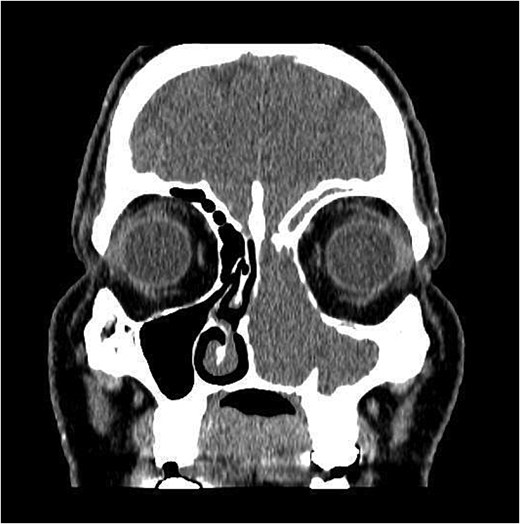

CT showed a heterogeneously enhancing mass completely occluding the left nasal cavity, left ethmoidal, maxillary and frontal sinuses, extending to left pterygopalatine fossa. It is associated with bony erosion of the posterior nasal septum and the left medial maxillary wall (Figs 1 and 2). Findings were suggestive of inverted papilloma vs sinonasal malignancy. Therefore, biopsy was recommended.

Coronal section of CT paranasal sinus with contrast soft tissue window showing the mass occupying the left nasal cavity and extending to maxillary and ethmoidal sinus.